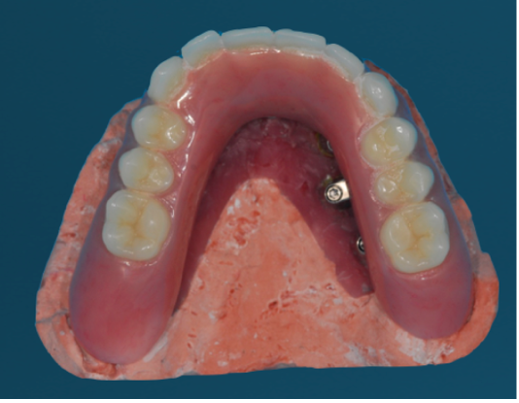

(42.) Fixed-removable prosthesis.

Figure 42

(43.) Fixed-removable prosthesis.

Figure 43

(44.) Fixed-removable prosthesis.

Figure 44

(45.) Fixed-removable prosthesis.

Figure 45

At the initial patient examination, several factors in addition to restoration shape should be considered when planning implant-supported restorations. History of periodontal disease, irregular maintenance visits, clinical appearance of the remaining teeth and soft tissue conditions may indicate increased risk of peri-implantitis. Patient dexterity, adaptability, willingness, and capability to carry out intended home care should be considered. Patient's mental conditions including dementia may influence the design of this as well as unrealistic patient expectations. A "High water original Branemark design" or no treatment may be indicated. Especially when implant location makes access, a fixed-removable design may be necessary to reduce risk of peri-implantitis may be indicated (Figures 42 through Figure 45). Considering that oral biofilm accumulation, even at two weeks post prosthetic insertion is documented, periodic removal of screw retained restorations is less effective than daily access to disrupt bacterial plaque accumulation.